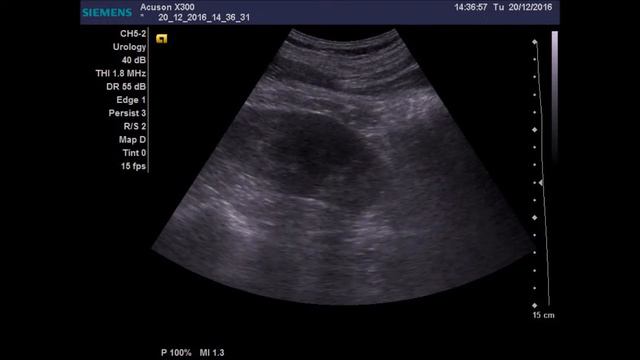

ОПИСАНИЕ: почечный синус справа имеет расщепленное строение, просвет ЧЛС сомкнут. ЗАКЛЮЧЕНИЕ: Нельзя исключить аномалию развития - удвоение правой почки. Видео ультразвукового исследования к лекции "УЗД опухолевидных образований органов мочевыделительной системы" - https://medprinting.ru/lekciya-ultrazvukovaya-diagnostika-opuholej-organov-mochevydelitelnoj-sistemy